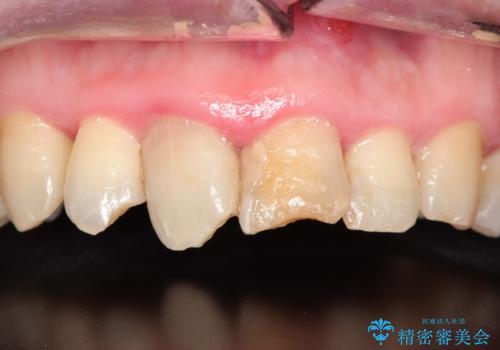

かけた前歯をきれいにしたい

- かけてしまった前歯をきれいにしたいとのことで来院されました。

レントゲンを撮影すると、根の神経の治療が必要なことがわかりました。

根管治療を行いセラミックを装着する計画としました。